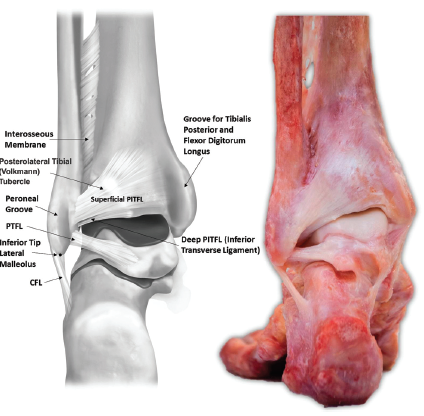

Picture 4. Posterior view of ankle (Williams 2015, pg 94).

The PITFL is also trapezoidal, with superior fibres attaching along the distolateral margin of the posterolateral tibial tubercle, then blending into the posterior tibial cortex (Williams et al., 2015). It is almost continuous into the interosseous membrane, located superior to the PITFL (Ebraheim, Taser, Shafiq, & Yeasting, 2006). The PITFL is made up a superficial ligament and deep ligament (often called the inferior transverse tibiofibular ligament). The superficial fibres are located 26.3mm from the inferior tip of the lateral malleolus, with the centre of the ligament 8mm from the posterolateral tibial plafond, while the deeper fibres are denser and attach to an oval-shaped insertion on both the fibula and tibia (see picture 5) (Williams et al., 2015).

Picture 5. Posterior view of ankle (Williams 2015, pg 94).